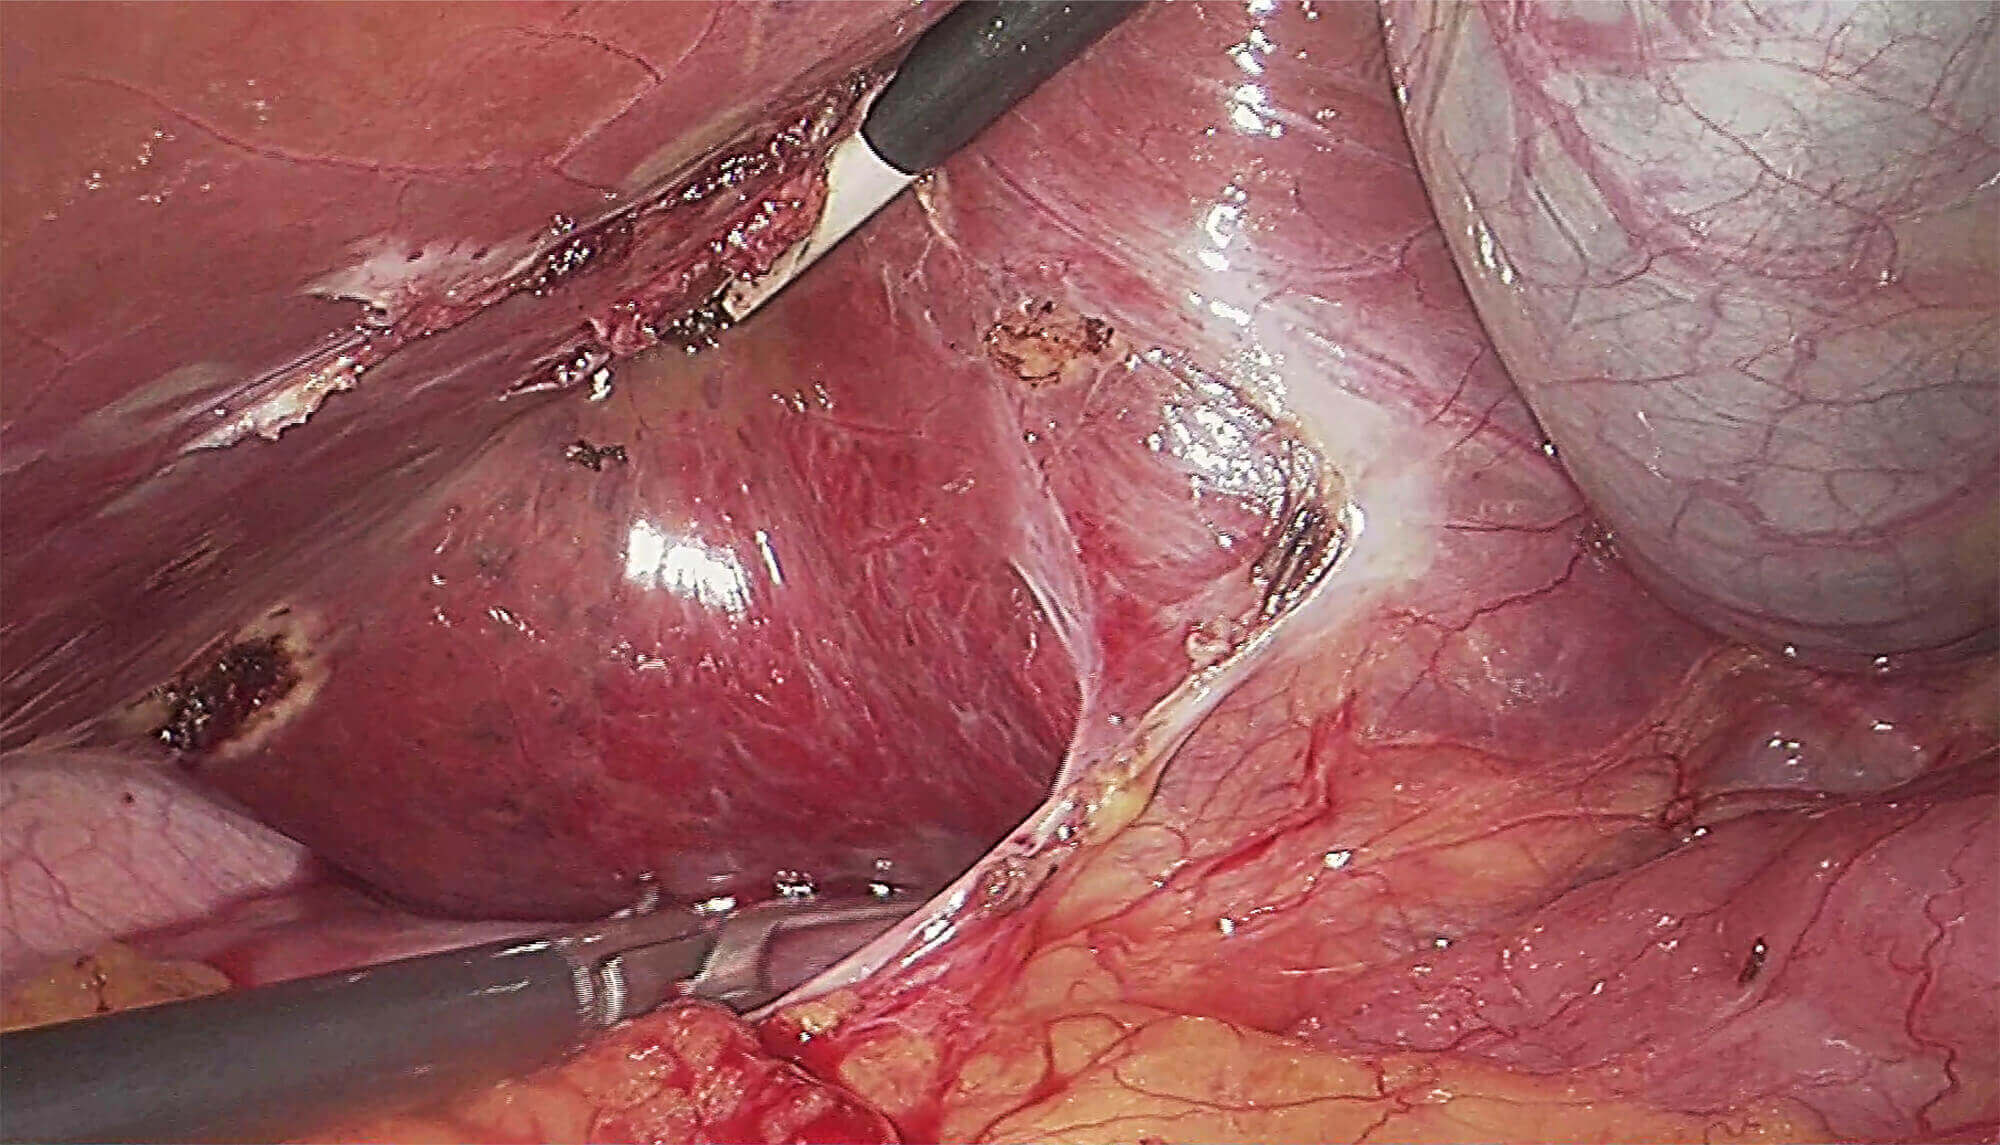

采用3片CMOS图像传感器,输出1920*1080P、60FPS全高清数字信号,提供稳定的腔镜视野,给予术者极佳的视觉体验,让手术更轻松,更精细!

提供两种冷光源选择方案,氙灯更亮更接近自然光,呈现图像效果更真实、更有层次感。LED灯寿命长更经济环保,且提供多光谱输出,可提高微小病变的检出率。

氙灯

LED灯